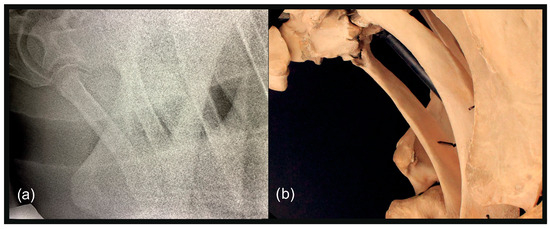

2.3. Radiographic Method

2.4. Classification System